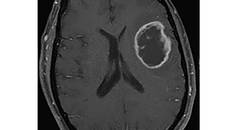

Challenge Case Report: A Woman With a Large Dural-Based Lesion

Javed Khader Eliyas, MD; Rimas V. Lukas, MDJaved Khader Eliyas, MD; Rimas V. Lukas, MD - Imaging & Testing